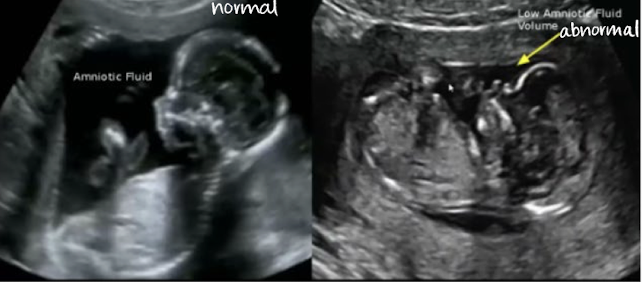

AF measurement method: subjective

“eyeball” assessment of amount of fluid

no actual measurements

better used early in gestation

successful with more experienced sonographer

leads to a more quantitative assessment

which has subjectively less AF?

right image